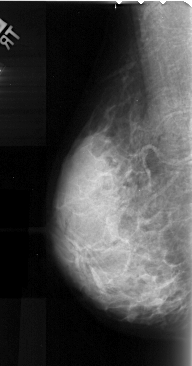

A_1052_1.RIGHT_MLO

A_1052_1.RIGHT_CC

RIGHT_CC LINES 5071 PIXELS_PER_LINE 2056 BITS_PER_PIXEL 16 RESOLUTION 42 NON_OVERLAY

RIGHT_MLO LINES 4996 PIXELS_PER_LINE 2146 BITS_PER_PIXEL 16 RESOLUTION 42 OVERLAY

FILE: A_1052_1.RIGHT_MLO.OVERLAY

TOTAL_ABNORMALITIES 1

ABNORMALITY 1

LESION_TYPE CALCIFICATION TYPE FINE_LINEAR_BRANCHING DISTRIBUTION LINEAR

ASSESSMENT 4

SUBTLETY 2

PATHOLOGY MALIGNANT

TOTAL_OUTLINES 1